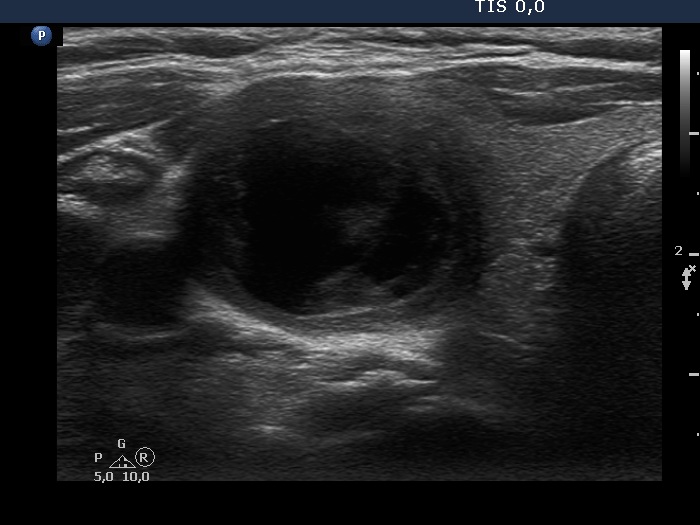

Ultrasonography. The thyroid was echonormal. There was a mixed moderately hypoechogenic-cystic nodule in the right lobe. The lesion presented various intranodular hyperechogenic granules including back wall figures, non-specific granules and a few typical comet-tail artifacts. There were other, difficult-to-classify bright granules. The latter could be either comet-tail artifacts or microcalcifications. There were several moderately hypoechogenic lesions in the left lobe.